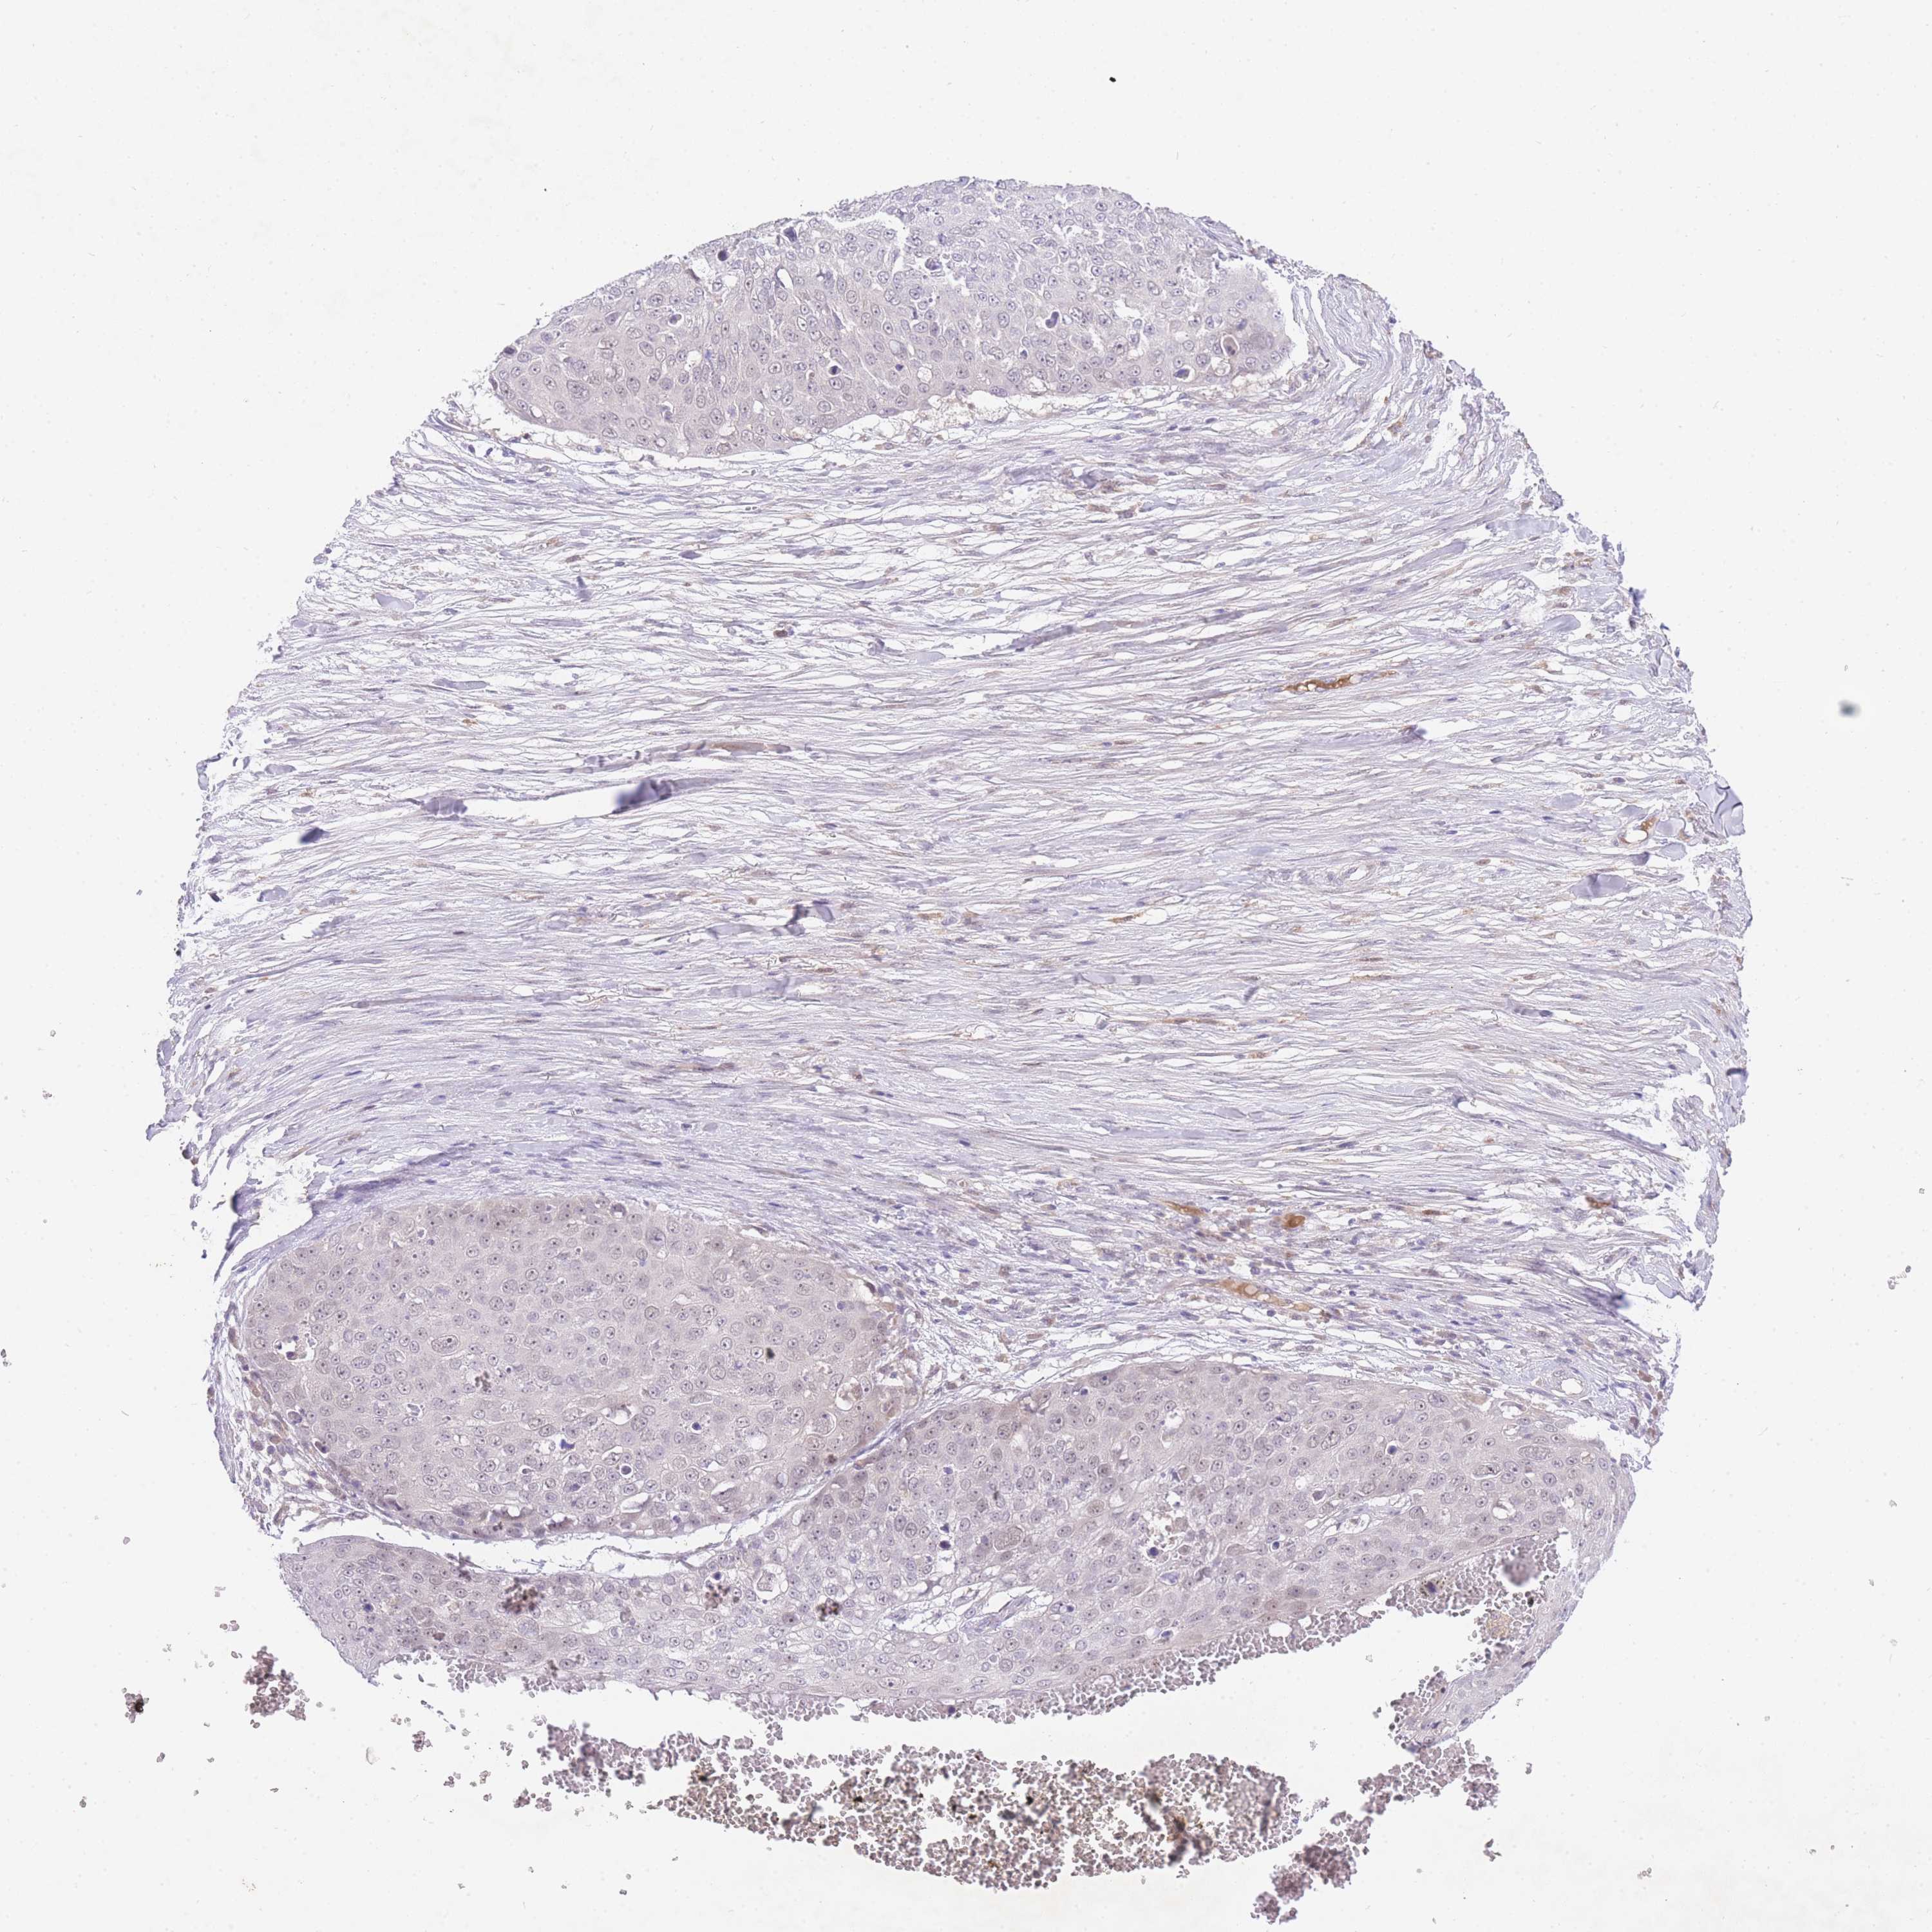

Basal cell and squamous cell cancer

SKIN CANCER - Protein expressioni

A mouse-over function shows sample information and annotation data. Click on an image to view it in a full screen mode. Samples can be filtered based on level of antibody staining by selecting one or several of the following categories: high, medium, low and not detected. The assay and annotation is described here.

Antibody stainingi

Antibody staining in the annotated cell types in the current human tissue is reported as not detected, low, medium, or high, based on conventional immunohistochemistry profiling in selected tissues. This score is based on the combination of the staining intensity and fraction of stained cells.

Each image is clickable and will lead to virtual microscopy that enables deeper exploration of all samples and also displays staining intensity scores, fraction scores and subcellular localization as well as patient and tissue information for each sample.

Antibody HPA049982

Staining

High

Medium

Low

Not detected

Intensity

Strong

Moderate

Weak

Negative

Quantity

>75%

75%-25%

<25%

None

Location

Nuclear

Cytoplasmic/membranous

Cytoplasmic/membranous,nuclear

Basal cell carcinoma

Squamous cell carcinoma, NOS

Squamous cell carcinoma, metastatic, NOS